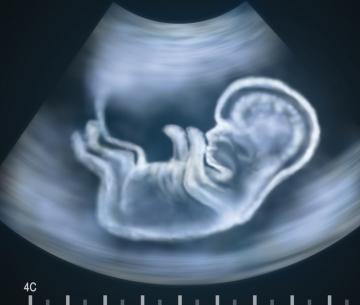

Se trata de una prueba que se realiza al final del primer trimestre de embarazo, entre la semana 12 y la 14. Con ella se busca detectar anomalías de tipo genético como el síndrome de Down. La prueba consiste en una ecografía por vía abdominal a través de la cual se mide el grosor de la zona de la nuca. En todos los bebés se acumula en esta parte líquido pseudo linfático, entre la piel y los tejidos blandos, lo normal es que su espesor no supere los 3 milímetros, si es mayor es un posible indicador de una anomalía Leer más sobre el artículo "¿En qué consiste el estudio de translucencia nucal?"